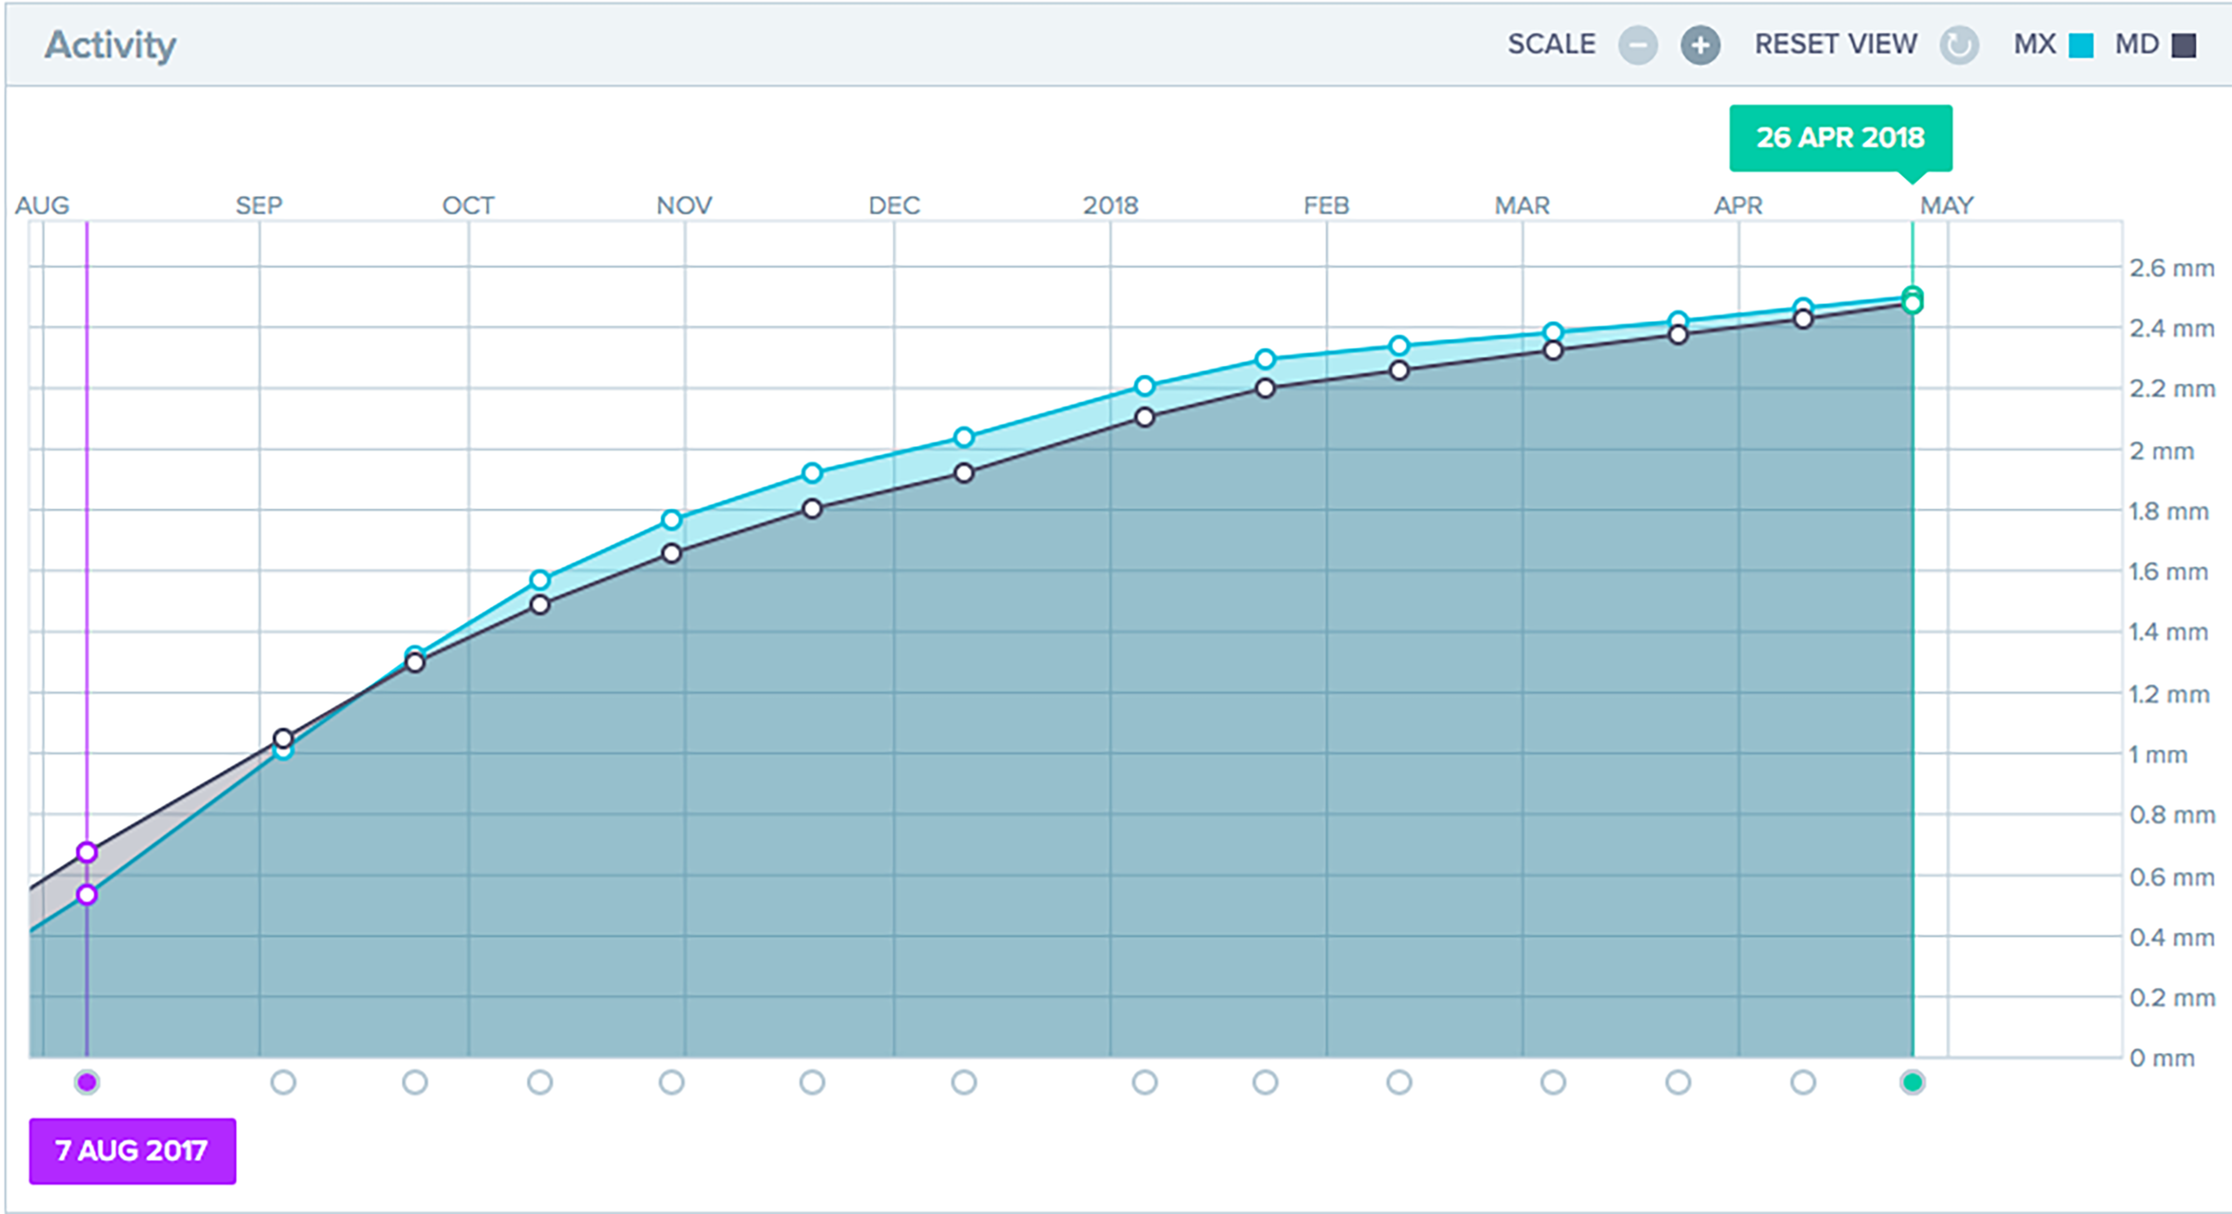

AI can be used to monitor treatment progress and track it against the proposed treatment plan and tooth movements. One of the current ways of incorporating this in your orthodontic practice is to use Dental Monitoring. Our internal clinical practice data from CCC Smiles in 2017 (n=125) shows on average AI technology has saved us 25% in number of appointments scheduled for those patients in comprehensive orthodontic treatment. Interestingly, there was no reduction in the number of appointments per patient for limited orthodontic treatments ranging from 3-9 months and an 15% increase in appointments scheduled for patient with fixed appliances! This study is a pilot and now ongoing for future publication.

AI can be used to monitor treatment progress and track it against the proposed treatment plan and tooth movements. One of the current ways of incorporating this in your orthodontic practice is to use Dental Monitoring. Our internal clinical practice data from CCC Smiles in 2017 (n=125) shows on average AI technology has saved us 25% in number of appointments scheduled for those patients in comprehensive orthodontic treatment. Interestingly, there was no reduction in the number of appointments per patient for limited orthodontic treatments ranging from 3-9 months and an 15% increase in appointments scheduled for patient with fixed appliances! This study is a pilot and now ongoing for future publication.

Do orthodontic treatments finish faster with AI? Treatment times depend on a number of factors and all virtual treatment monitoring detects is progress, breakages and aligner fit (tracking) against the proposed treatment plan. If all other factors are favourable, we should see a reduction in aligner unseats and be able to assess breakages quickly. Our pilot data shows aligner patients are more compliant with prescribed wear time when AI technologies are used – the compliance rose from 50% to 90%. This shows that we should be f

inishing treatments earlier and more predictably. This is yet to be shown in a clinical trial.